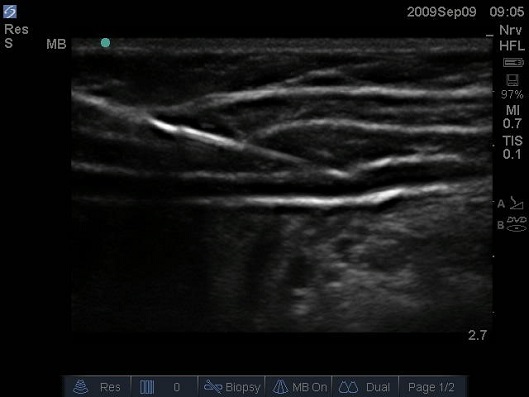

Figure 5 Ultrasound image of lateral abdominal wall of infant, needle inserted from anterior to posterior using an in plane needling technique. A 10MHz linear probe is positioned in the transverse plane midway between the iliac crest and costal margin.